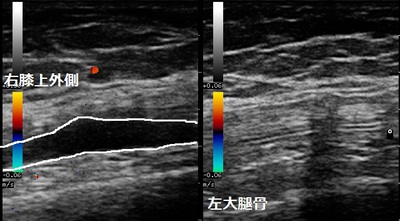

鶴ヶ島市 主婦 右膝関節の痛み 膝関節水腫

右膝関節上部(患部) 左膝関節同部位(正常側)

主婦の膝は見た目にも少し腫れています。熱感も有りますので関節炎を起こしています。膝を深く曲げ

ようとすると痛みが出て、深く曲げられません。超音波検査で右ひざ関節に関節液(水)が貯留してい

ました(画像左の白線の囲み)。主婦は水が溜まっているとは思っていなかったようです。